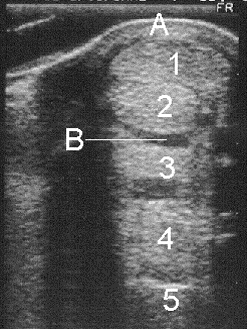

Label the ultrasound of the equine distal limb (transverse)

B - Tendon sheath